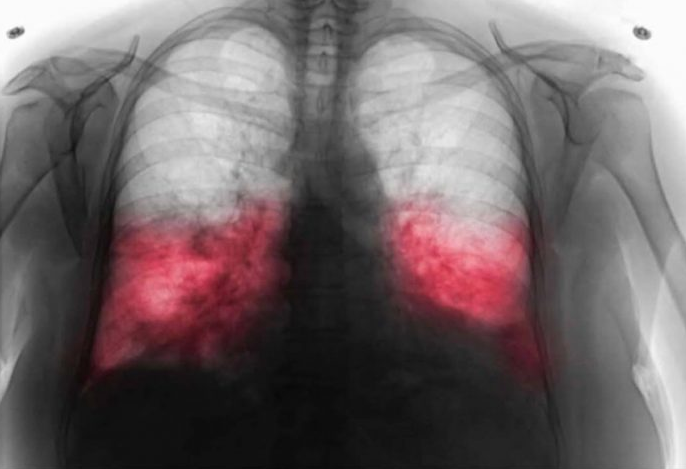

Kada postoji sumnja na hodajuću upalu pluća, ljekar će najprije razgovarati s pacijentom o simptomima i pažljivo poslušati pluća. U mnogim slučajevima potrebne su dodatne analize kako bi se potvrdila dijagnoza.

- To može uključivati laboratorijske nalaze, briseve respiratornih puteva ili rendgenski snimak pluća. Tačna dijagnoza je veoma važna, jer uzročnik ove bolesti često ne reaguje na uobičajene antibiotike koji se koriste kod drugih infekcija.